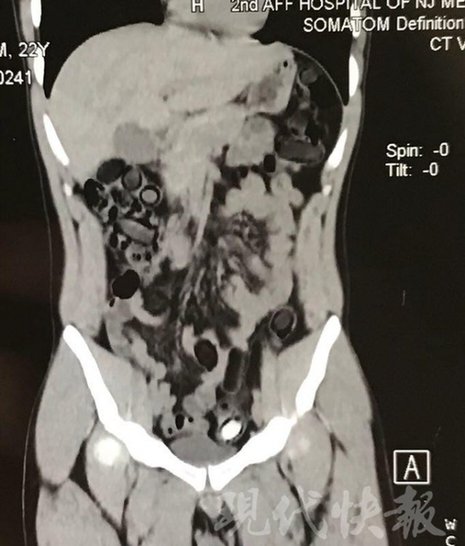

小伙體內(nèi)藏毒300余克 CT掃描圖密密麻麻

運(yùn)毒小伙:希望被判處死刑

由于毒品在體內(nèi)一旦泄露有可能致命,警方第一時(shí)間將阿永帶到醫(yī)院進(jìn)行檢查。CT 掃描的結(jié)果顯示,阿永體內(nèi)布滿了密密麻麻的白色圓柱狀固體,就像一粒粒的蠶蛹。在南京市公安局鼓樓分局二板橋派出所,阿永分四次排出了毒品,毛重369.99克。經(jīng)訊問(wèn),阿永交代了自己全部的犯罪事實(shí)。目前,阿永已被刑事拘留。